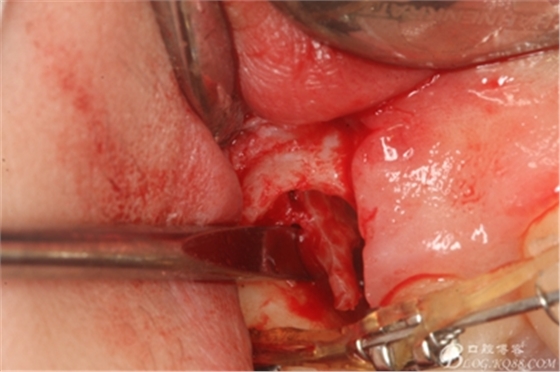

圖16.微創(chuàng)挺挺松近中根面部分,從16與14之間間隙出來

圖17.血管鉗取出近中部分15牙根

圖18.取出近中部分后,接著挺松15牙根的遠中部分

圖19.挺松后,15的遠中部分仍從合面狹小間隙通過取出。